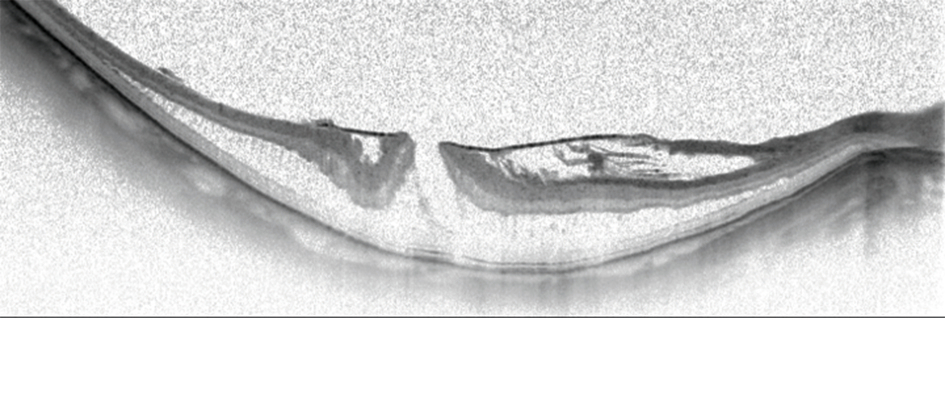

[caption id="attachment_14161" align="alignleft" width="945"] Horizontal OCT scan of a myopic foveoschisis with a premacular membrane[/caption] Preoperative visual acuity is the main factor influencing functional outcomes after vitrectomy for myopic foveoschisis. With this information in mind, retina specialists aiming to improve their results should consider operating sooner rather than later, said Ramin Tadayoni MD, PhD, at the 18th EURETINA Congress in Vienna, Austria. “Of course, we can also do better for our patients by using modern surgical techniques and imaging technologies. But, we will have better results if the indication for surgery is good. If the goal is to achieve BCVA [best-corrected visual acuity] better than 20/40, then surgery should be done when the vision is 20/50 or better. We should not wait for the vision to get worse,” said Dr Tadayoni, Professor of Ophthalmology, Paris 7 University, Lariboisière Hospital & OphtalmoPôle, Paris, France.